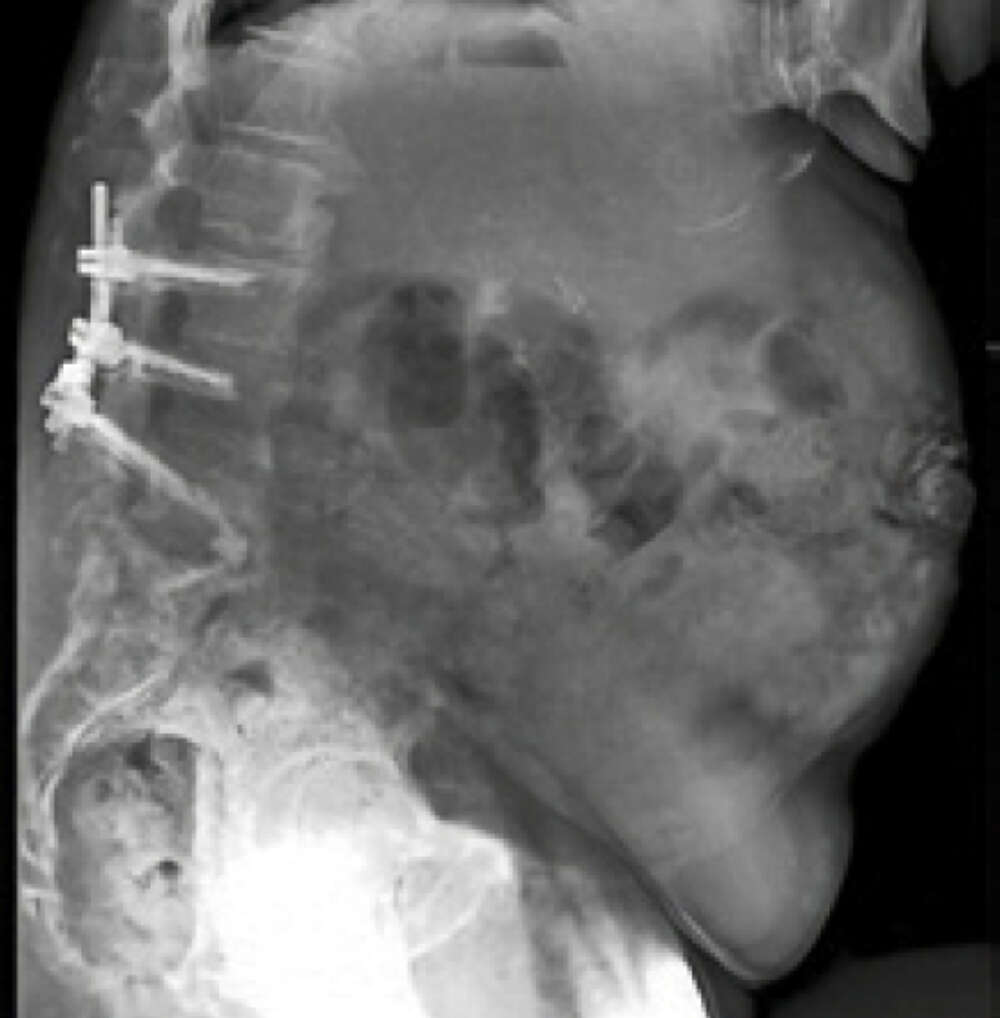

Fixed Sagittal Plane Deformity1

Patient History:

- 69 y/o female with history of multiple prior spine surgeries including L3-S1 fusion

- Presented with progressive pain and disability from sagittal plane deformity

- Symptomatic SI joint arthropathy likely accelerated by her prior lumbosacral fusion. 4/5 provocative maneuvers positive. Positive response to SI injection

- Failed to improve with exhaustive non-surgical management including PT and injections

Surgical Treatment:

- T10-pelvis posterior fixation and fusion

- L4 pedicle subtraction osteotomy (PSO)

- Bilateral placement of iFuse 3DTM implants using the Bedrock® technique

- Four points of SIJ fixation

Post-op:

- PI-LL: 43° to 7°, C7-SVA: 24cm to 5cm

- Back and SI joint pain improved post-operatively. Improvement persisted at 2 years.2